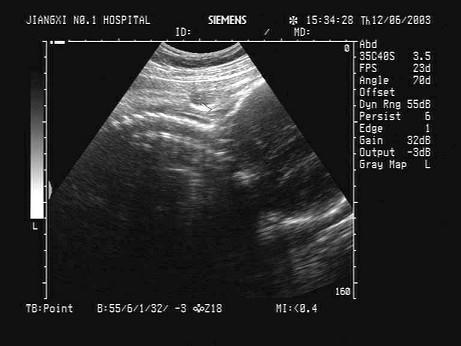

问题 某胎儿超声声像图如下,最可能的诊断为?(?)

选项 A.脐带绕颈1周 B.脐带绕颈2周 C.脑积水 D.正常声像图 E.脐带绕颈3周

答案 A